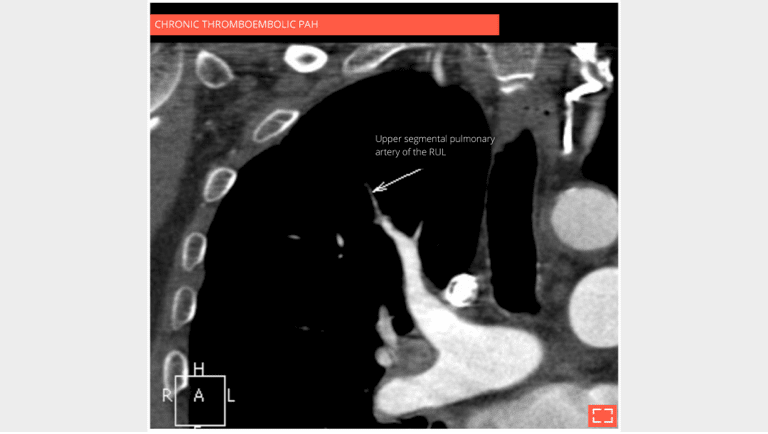

The CT scan with contrast medium injection to check for pulmonary artery obstruction shows the small size and distal thrombosis of peripheral pulmonary arteries, confirming chronic thrombosis. Ventilation-perfusion scintigraphy is the recommended exam for screening for these anomalies.

3. Vascular mosaic attenuation

Vascular mosaic attenuation